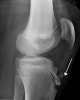

X-ray : 오스굿 슐라터병(Osgood-Schlatter disease, Maid's knee)

초기에는 경골 골절 골단선은 불규칙하게 분리되어 있으나, 말기에는 경골 결절의 세분화가 두드러지게 되며 간혹 슬개건 내에 석회화가 나타나기도 합니다.

한편, 경골 결절이 완전히 떨어진 경우에는 골편이 상방으로 회전 전위되기도 합니다.